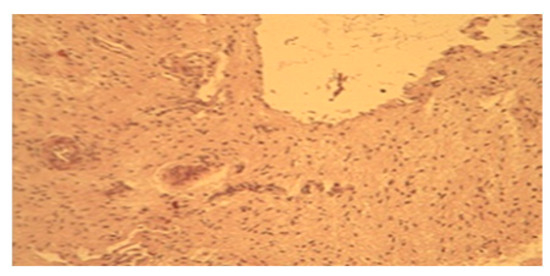

3.5. From 15th to 18th Postpartum Day

3.6. From 19th to 21st Postpartum Day